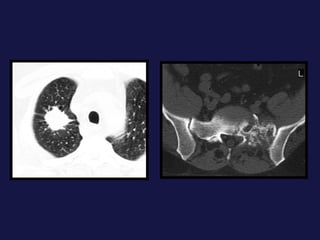

Metástasis. Cerebro. Hueso. Hígado. Suprarrenales.

Metástasis al pulmón. El pulmón y el hígado son los mas FREC. Pueden tener varios tamaños. Imágenes nodulares, únicas o múltiples. Pueden cavitarse y calcificación.

Metástasis. Cerebro. Hueso.Hígado. Suprarrenales.

Metástasis al pulmón.El pulmón y el hígado son los mas FREC. Pueden tener varios tamaños. Imágenes nodulares, únicas o múltiples. Pueden cavitarse y calcificación.